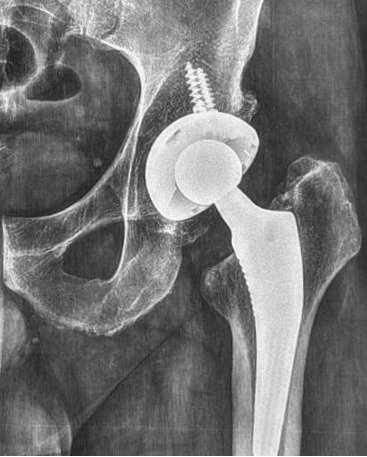

-La prótesis total de cadera se llama TOTAL porque reemplaza fémur y acetábulo. En caso de sólo reemplazar fémur y colocar una copa móvil en el acetábulo sería una prótesis bipolar o de dos cabezas. Su indicación es en paciente seniles de baja demanda. Siempre las vamos a preferir a una monoblock (Thompson, AustinMoore, Lazcano), el precio no justifica el riesgo de artrocatadiasis secundaria o protrusión intrapélvica.

-Un buen sistema bipolar permite intercambiar cabezas de copas con vástagos tanto cementados como no cementados y tamaños de cabezas. Eso lo hace mas preciso pero más caro.

-En la foto se muestra un vástago cementado de revisión Reactiv y una copa Moonstone de Evolutis.

-Mas aún, por abordaje vía anterior se puede colocar una prótesis total de cadera de doble movilidad.

Prótesis total de cadera con inserto móvil doble movilidad